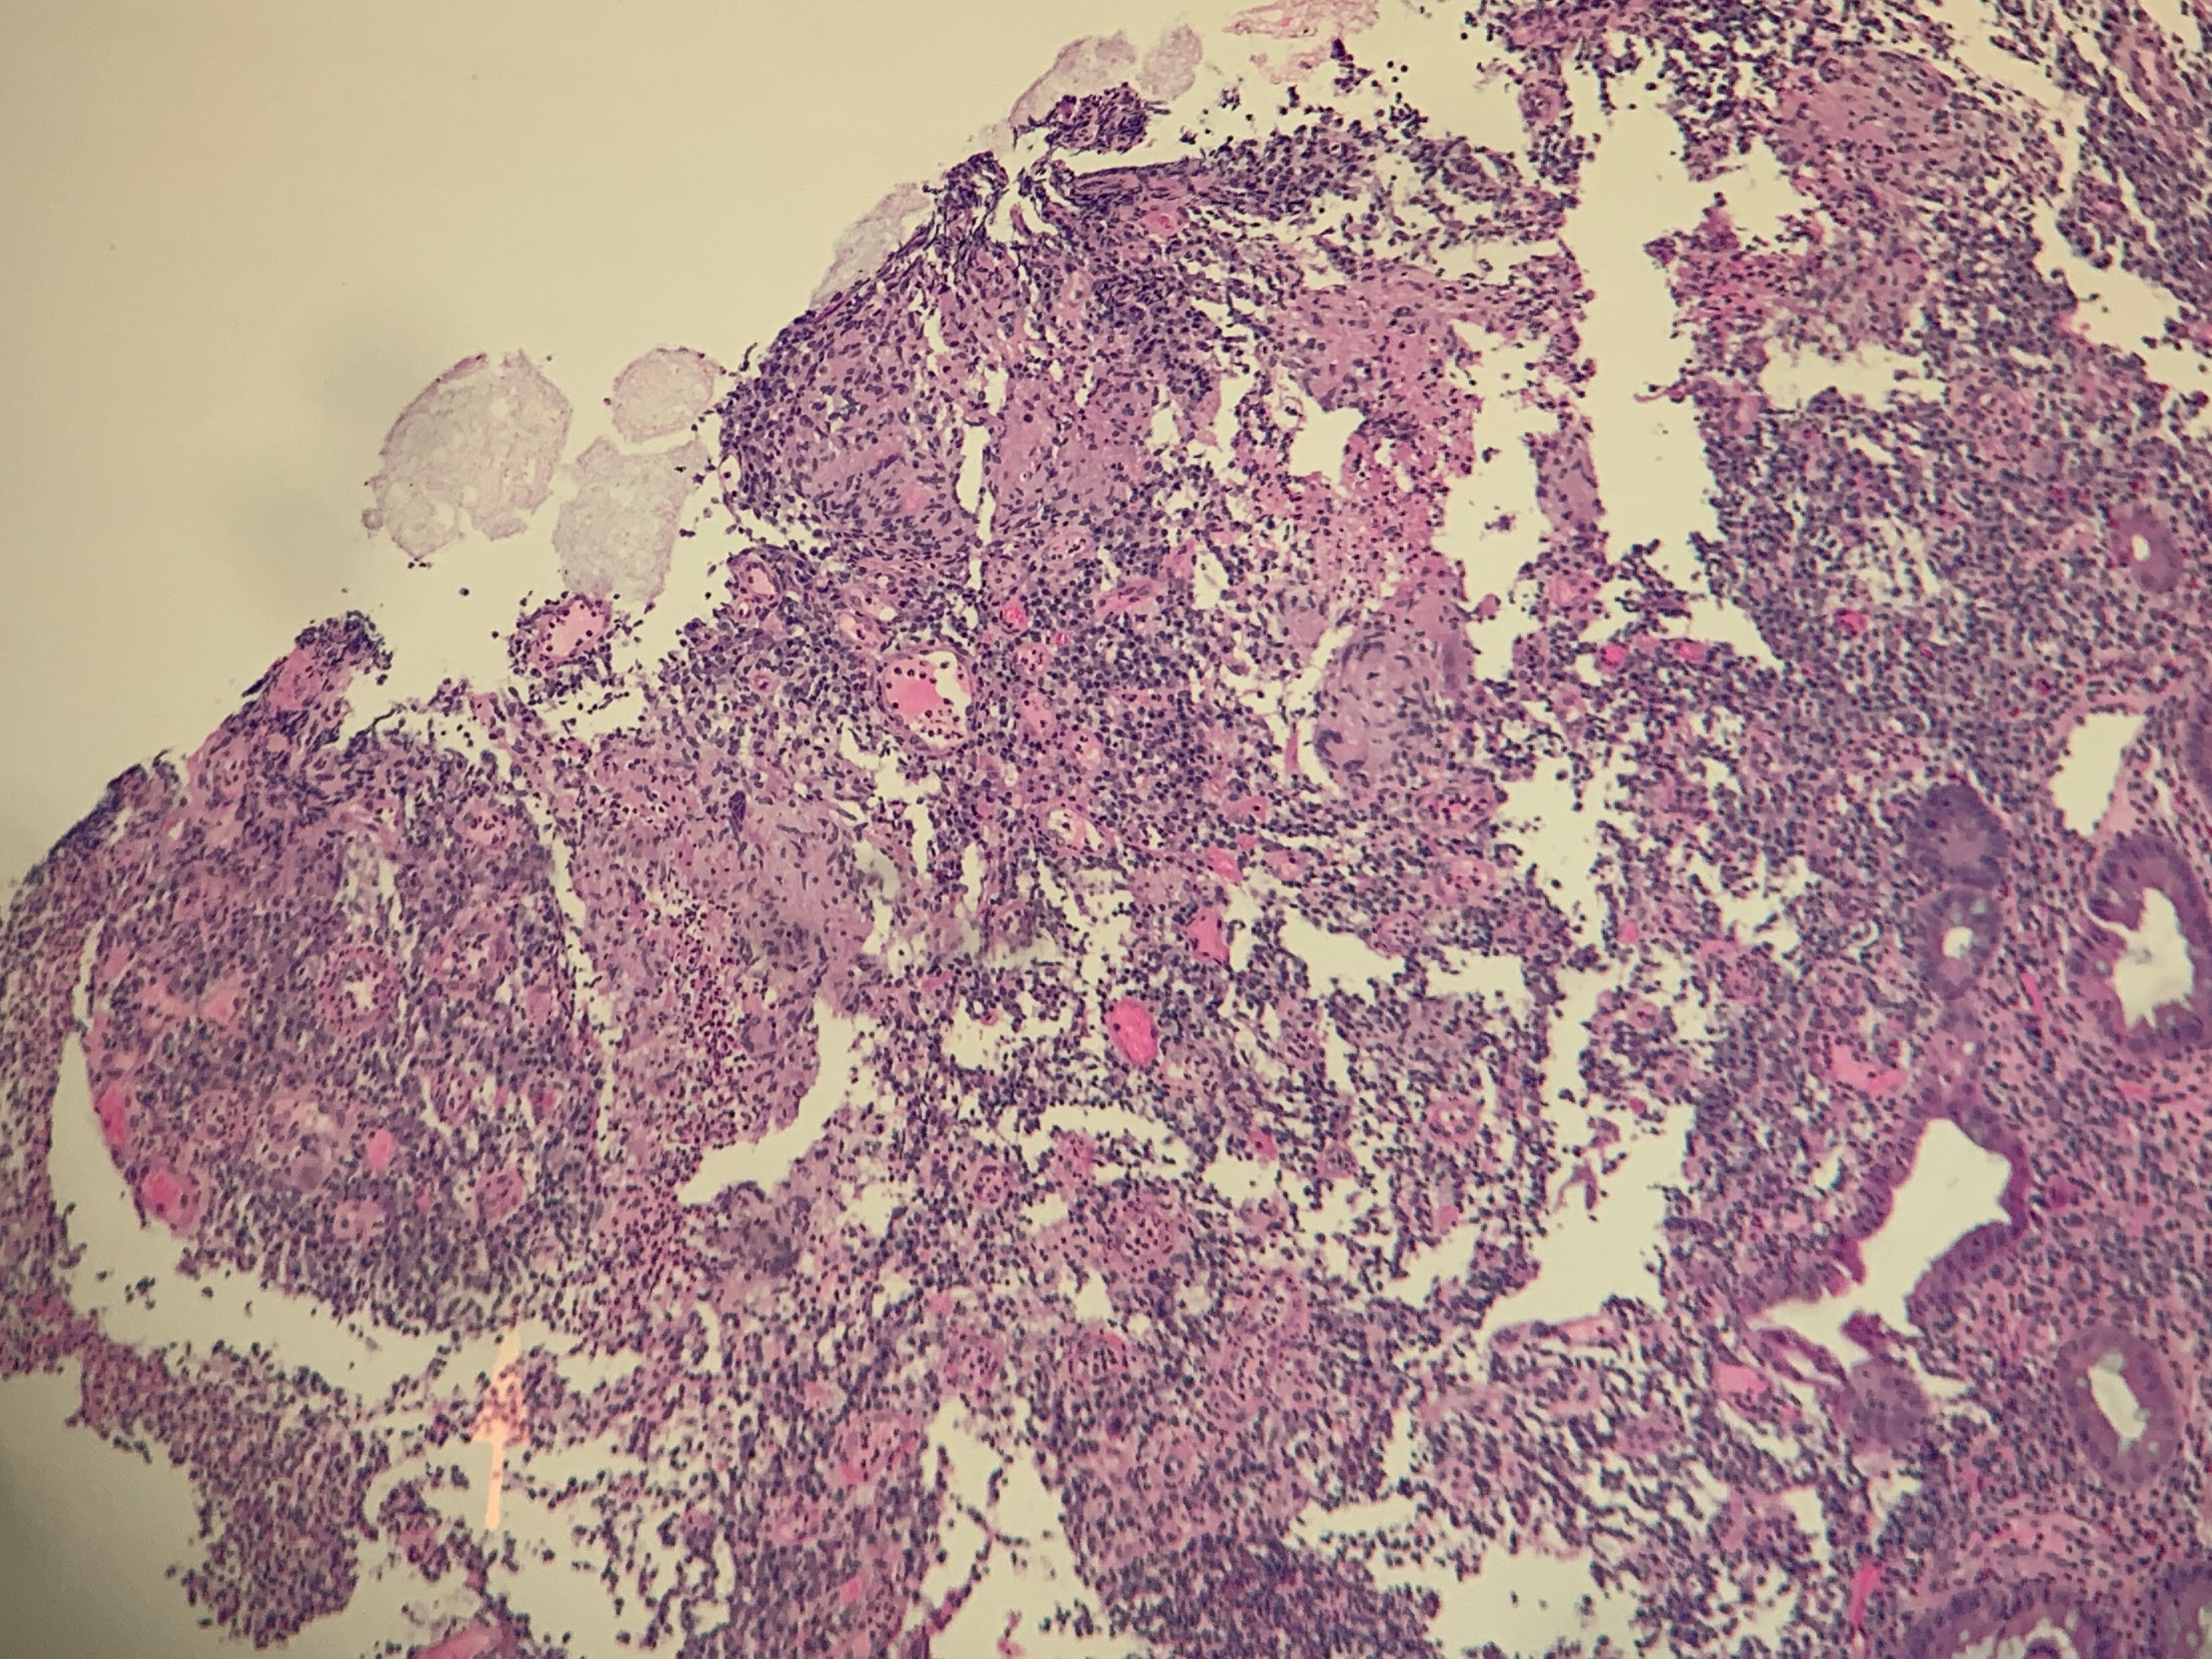

Case Report: 51 year old man with worsening pneumonia while hospitalized

Christopher Cirino, DO, MPH